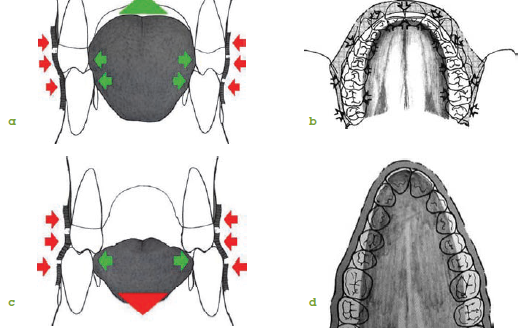

Indices et Mensurations

Image : Exemple d’indices et mensurations pour le diagnostic des anomalies dento-alvéolaires.

Examen Radiologique

Image : Radiographie de face pour le diagnostic des anomalies dento-alvéolaires.